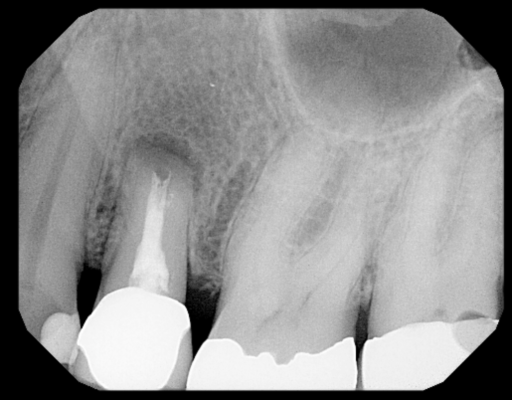

How would you guys proceed with this case? I am assuming we will need to rebuild the facial wall entirely. Thought about using a titanium mesh membrane tacked down after scrubbing the remaining socket out and placing pt on antibiotics. Question is should we go ahead and graft or wait to heal before grafting and membrane placement?

Is this a good case for immediate implant placement at the time of extraction? If so, what protocol should be done to insure the periapical infection is cleaned out and doesn’t result in implant failure? Thanks!